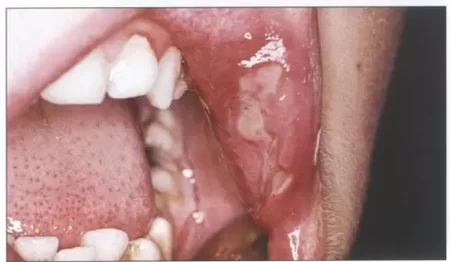

Zmiany pierwotne i wtórne jamy ustnej

nazwij przedstawione wykwity pierwotne i wtórne